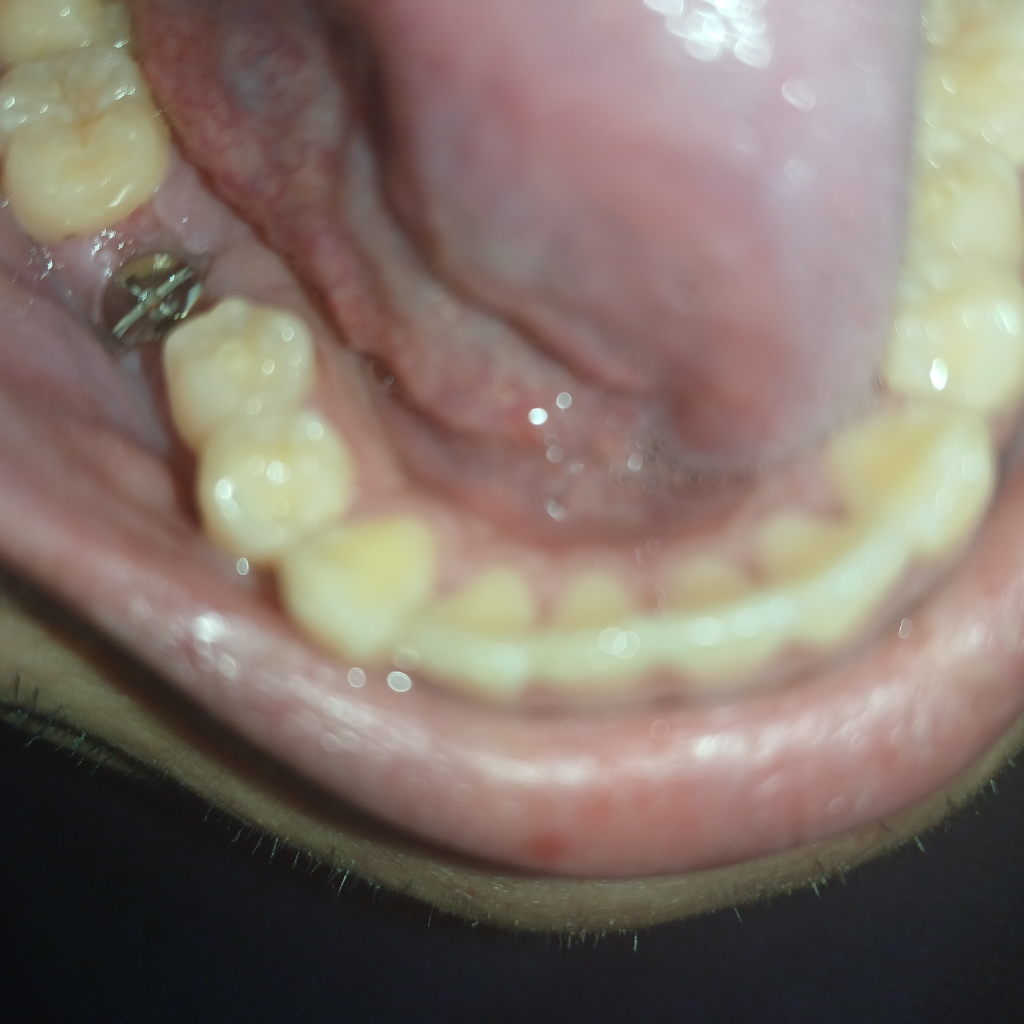

임플란트를 하고 나서는 인플란트 상부에 보철물이 올리기 위해서 잇몸이 아무는 장치물을 결속해 놓는 경우도 있습니다

임플란트 덮게 나사는 잇몸 밖으로 노출되는 것이 정상입니다. 지금 사진의 것도 정상적인 것이니 그냥 두면 됩니다.

잇몸을 만들기 위해서 뚜껑을 닫아 놓으셧다고 생각하시면됩니다. 본을 뜰때 저걸 제거하고 본을 뜹니다.

보통 뚜껑을 교체하는 수술이 두번째 수술인데 처음에는 잇몸 속에 묻혀있는 작은 뚜껑을 넣어 임플란트 뿌리가 뼈와 잘 융합되도록 기다리는 시간을 가지고, 두번째 수술에서는 잇몸 위로 튀어나온 큰 뚜껑(힐링 어버트먼트)을 달아 주변 잇몸 높이를 맞춰주고 본 뜰 준비를 합니다.